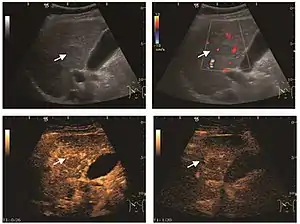

Early hepatocellular carcinoma (Early HCC)

The suggestive appearance of early HCC on 2D ultrasound examination is that of hypoechoic nodule, with distinct pattern, developed on cirrhotic liver. Hypoechoic appearance is characteristic of moderate/poorly differentiated HCC, with low or absent fatty changes. Rarely, HCC may appear isoechoic, consist of a tumor type with a higher degree of differentiation and therefore with slower development. Another common aspect is "bright loop" or "nodule-in-nodule" appearance, hypoechoic nodules in a hyperechoic tumor.

Spectral Doppler characteristics of early HCC overlap those of the dysplastic nodule, as they are represented by the presence of portal venous signal type or arterial type with normal RI (well differentiated HCC) or increased RI (moderately or poorly differentiated HCC). The CFM exploration identifies a chaotic vessels pattern.

On CEUS examination, early HCC has an iso- or hypervascular appearance during the arterial phase followed by wash out during portal venous and late phase. There are studies showing that the wash out process is directly correlated with the size and features of neoplastic circulatory bed. Thus, highly differentiated HCC illustrates the phenomenon of late or even very late "wash out" while poorly differentiated HCC has an accelerated wash out at the end of arterial phase. It is therefore mandatory to analyze all these three phases of CEUS examination for a proper characterization of liver nodules. Tumor wash out at the end of the arterial phase allows the HCC diagnosis with a predictability of 89.5%. Some authors consider that early pronounced contrast enhancement of a nodule within 1–2 cm developed on a cirrhotic liver is sufficient for HCC diagnosis. These results prove that for a correct characterization of the lesions it is necessary to extend the examination time to 5 minutes or even longer.